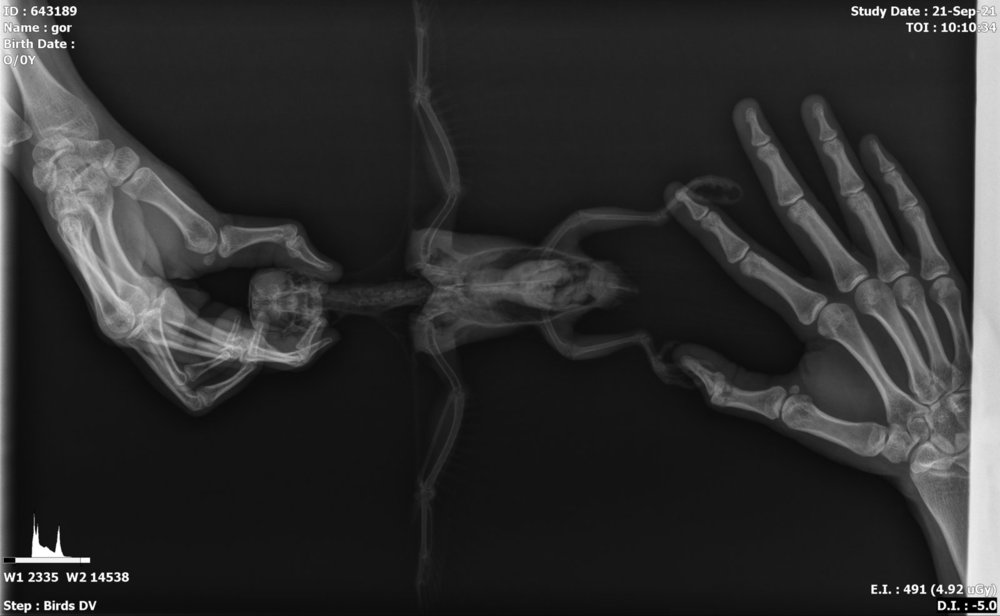

Кандидоз и бактериальная инфекция дыхательных путей у солнечного аратинги

сейчас был в клинике, сделали рентгена и взяли мазки.

Диагноз: кандидоз и бактериальная инфекция. Какая инфекция - не смогли обьяснить. Озвучили что прогноз неблагоприятный. Назначили два препарата, в течение пяти дней капать в клюв, на пятый день контрольный рентген.

Снимок и назначения прилагаю.

Рентген лучше выложить оригинал, а не экранку.

к сожалению рентген только в таком виде и никак иначе((

Такой рентген удалось выбить. Жду от них информацию по назначенным препаратам.

Рентген лучше выложить оригинал, а не экранку

94763001-3C6F-4C3E-94D7-384C97D583DE.jpeg